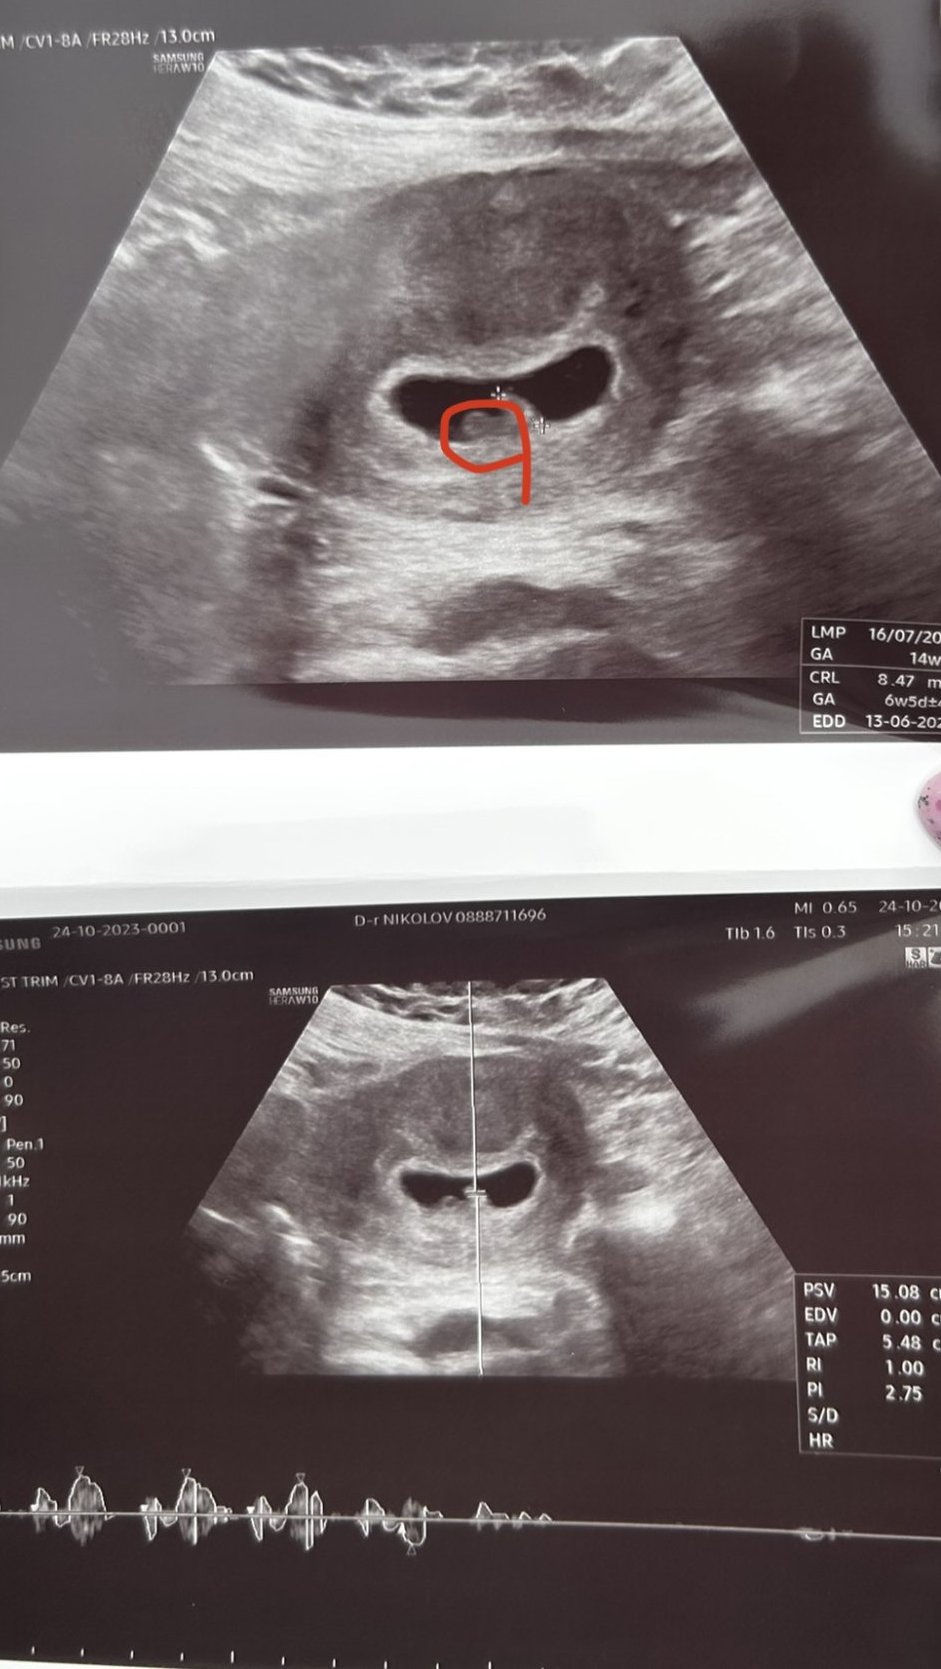

Здравейте, може ли малко помощ за разчитането? Как ви се струва?

На горната снимка е измерил плода, а другата част (която съм оградила в червено)на самата снимка какво е? Извинявам се, за глупавият въпрос, просто ми е много интересно. Благодаря предварително Heart

Последна редакция: чт, 26 окт 2023, 18:47 от zozulyn

Мисля,че на втората снимка е пулса...